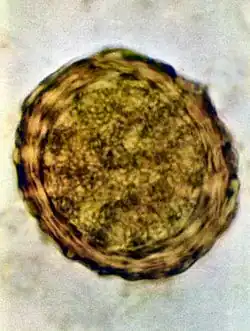

Fertile egg as can be seen in a microscope

Fertile egg in human faeces (detail)

Ascaris lumbricoides is characterized by its great size. Males are 2–4 mm (0.08–0.2 in) in diameter and 15–31 cm (5.9–12 in) long. The male's posterior end is curved ventrally and has a bluntly pointed tail. Females are 3–6 mm (0.1–0.2 in) wide and 20–49 cm (7.9–19 in) long. The vulva is located in the anterior end and accounts for about one-third of its body length. Uteri may contain up to 27 million eggs at a time, with 200,000 being laid per day. Fertilized eggs are oval to round in shape and are 45–75 μm (0.0018–0.0030 in) long and 35–50 μm (0.0014–0.0020 in) wide with a thick outer shell. Unfertilized eggs measure 88–94 μm (0.0035–0.0037 in) long and 44 μm (0.0017 in) wide.[9]